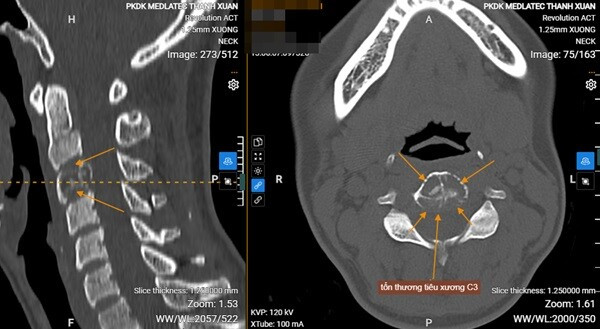

Qua thăm khám lâm sàng, bác sĩ phát hiện các dấu hiệu bất thường tại cột sống cổ, bệnh nhân được chỉ định chụp cắt lớp vi tính để đánh giá chi tiết hơn. Kết quả cho thấy tổn thương tiêu xương tại thân đốt sống C3, nghi ngờ là u xương thứ phát, nên tiếp tục đề nghị chụp MRI bổ sung để làm rõ chẩn đoán. Kết quả MRI ghi nhận hình ảnh tổn thương gây xẹp thân đốt C3, theo dõi di căn (metastases). Dựa trên cơ sở kết quả cận lâm sàng đã thực hiện, bác sĩ chẩn đoán mắc ung thư vú di căn xương đốt sống cổ C3. Chị L sau đó được chuyển sang một bệnh viện lớn điều trị.

Tổn thương tiêu xương thân đốt C3, phá vỡ vỏ xương, đẩy lùi vào ống sống của bệnh nhận ghi nhận trên hình ảnh chụp CT.